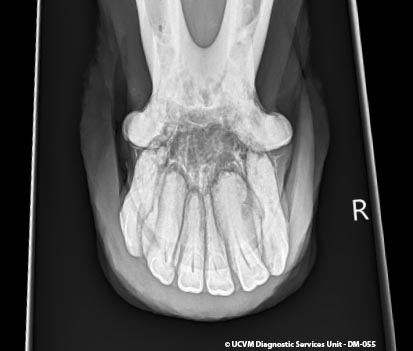

Species: Equid, Horse

Specimen: Teeth

Shown: EOTRH equine odontoclastic tooth resorption and hypercementosis